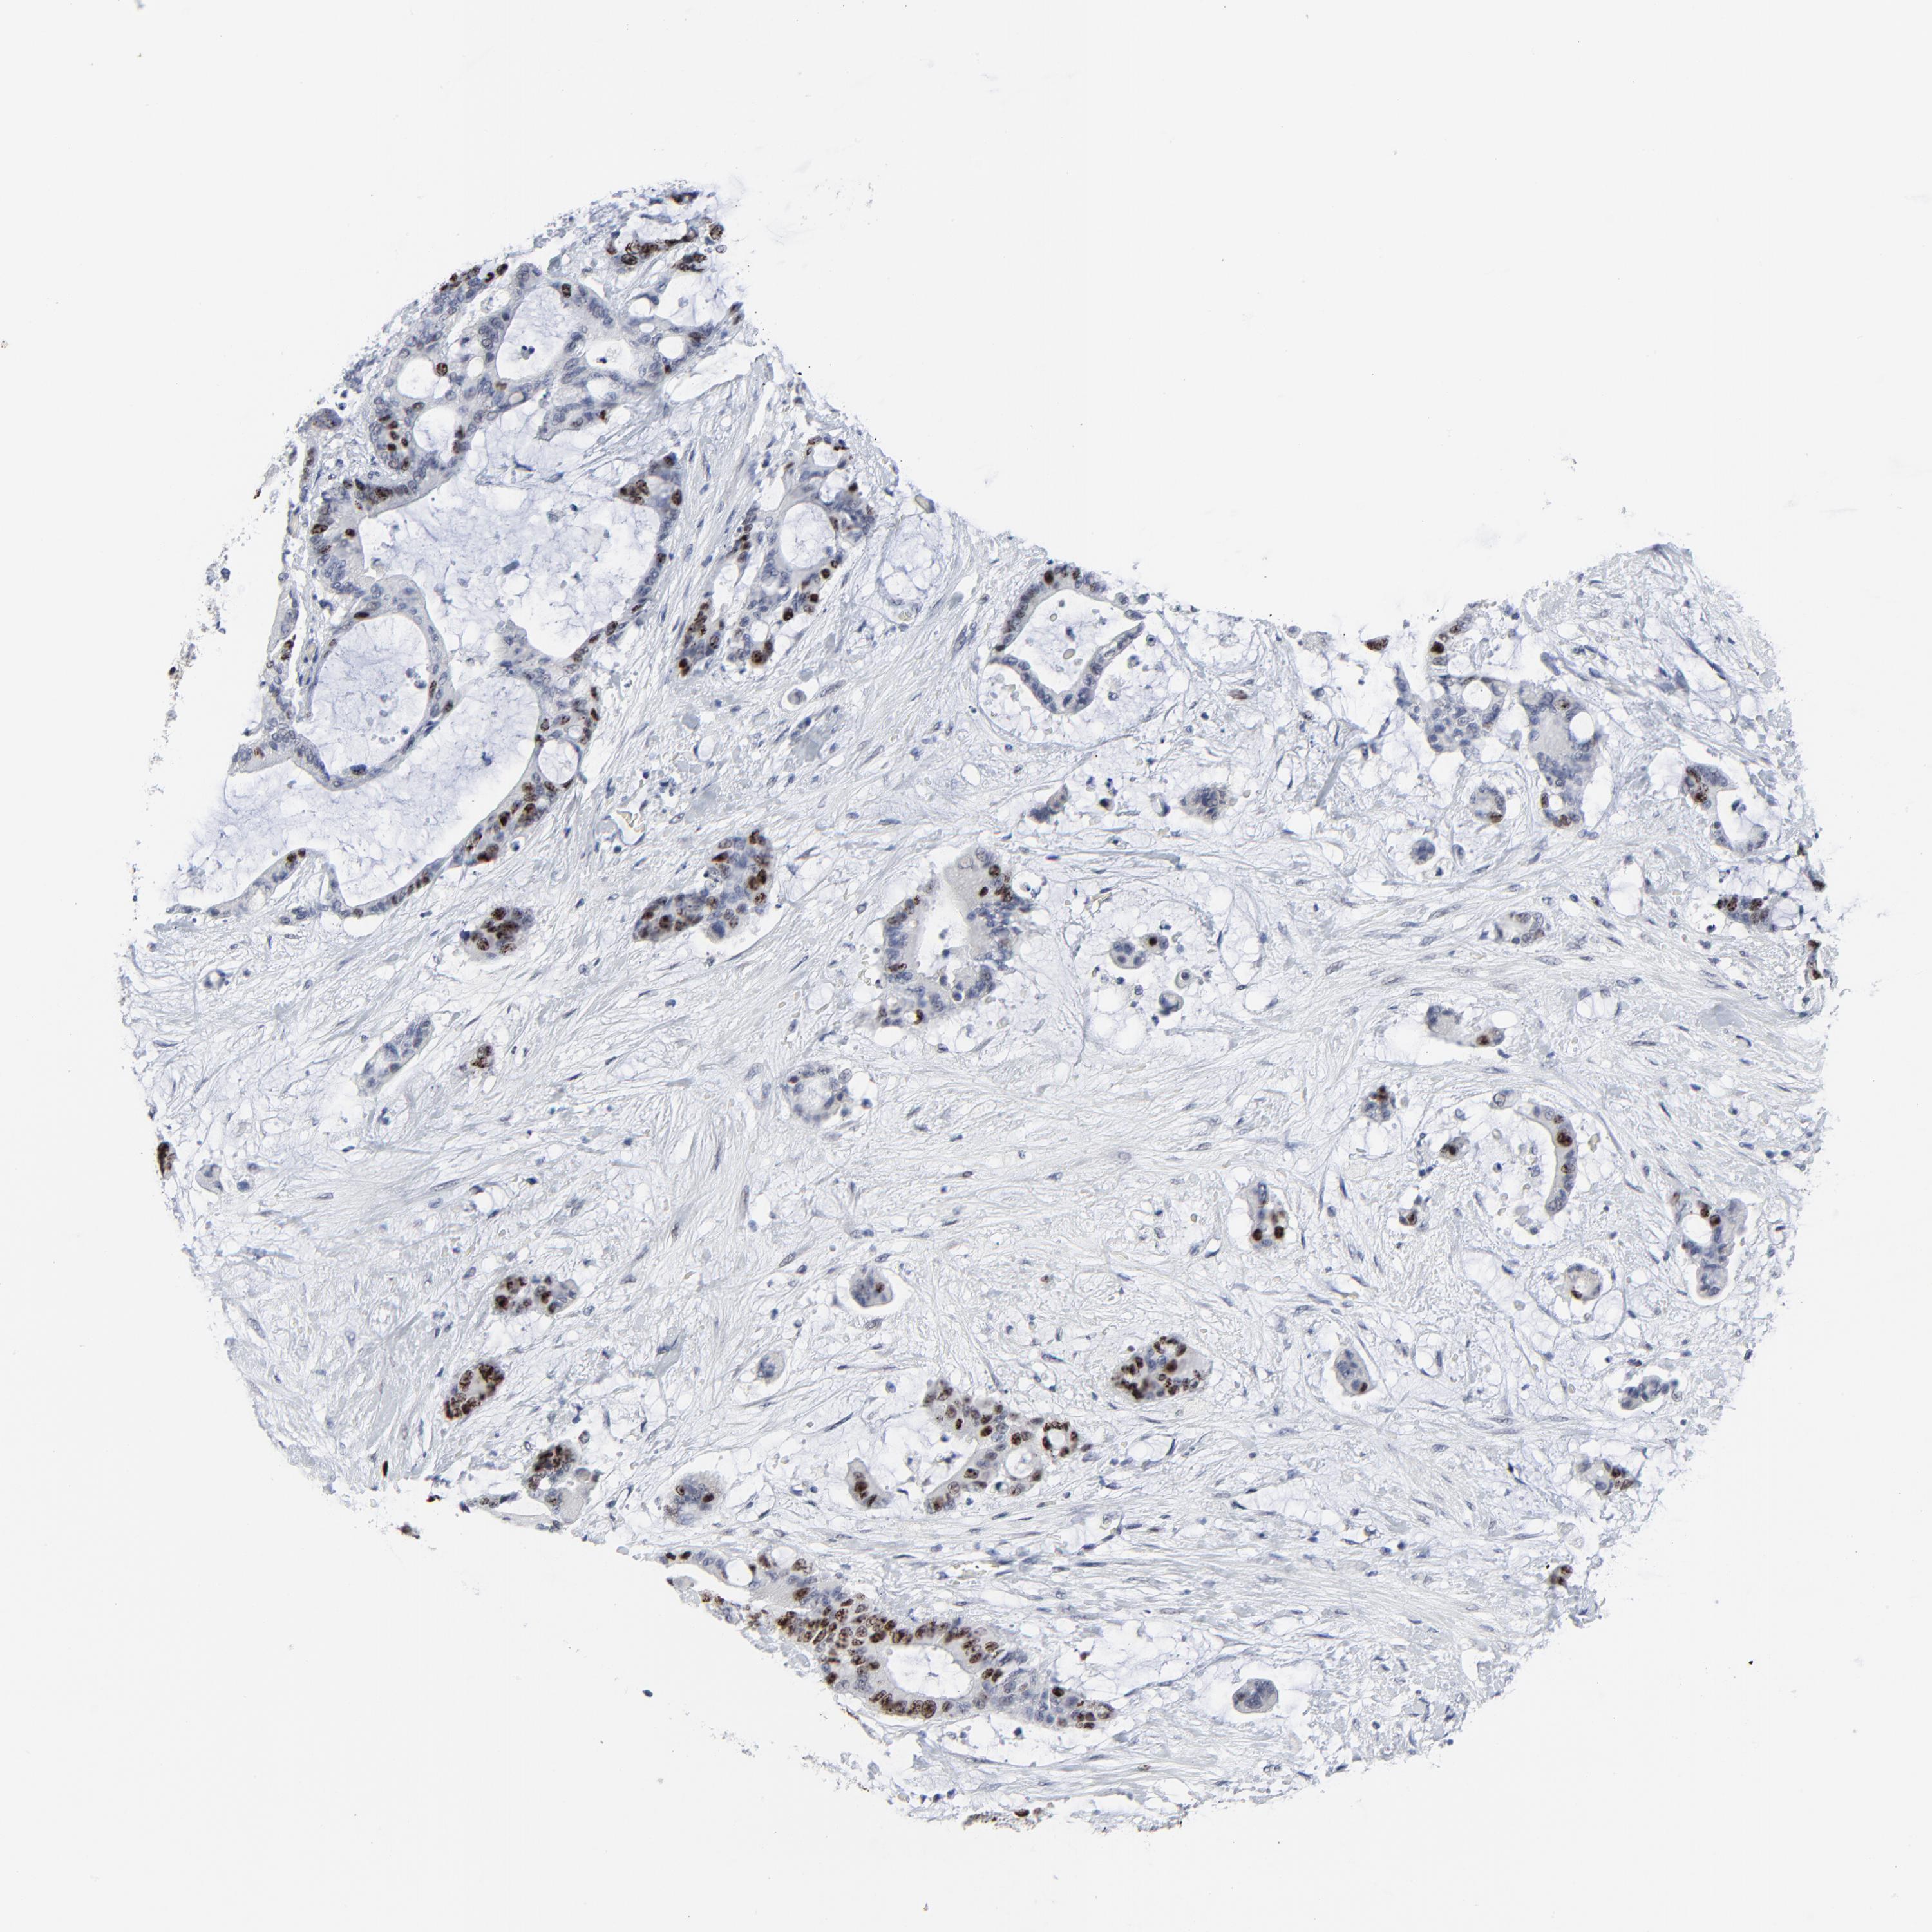

LIVER CANCER - Protein expressioni

A mouse-over function shows sample information and annotation data. Click on an image to view it in a full screen mode. Samples can be filtered based on level of antibody staining by selecting one or several of the following categories: high, medium, low and not detected. The assay and annotation is described here.

Note that samples used for immunohistochemistry by the Human Protein Atlas do not correspond to samples in the TCGA dataset.

Antibody stainingi

Antibody staining in the annotated cell types in the current human tissue is reported as not detected, low, medium, or high, based on conventional immunohistochemistry profiling in selected tissues. This score is based on the combination of the staining intensity and fraction of stained cells.

Each image is clickable and will lead to virtual microscopy that enables deeper exploration of all samples and also displays staining intensity scores, fraction scores and subcellular localization as well as patient and tissue information for each sample.

Antibody HPA003145

Staining

High

Medium

Low

Not detected

Intensity

Strong

Moderate

Weak

Negative

Quantity

>75%

75%-25%

<25%

None

Location

Nuclear

Cytoplasmic/membranous

Cytoplasmic/membranous,nuclear

Cholangiocarcinoma

Carcinoma, Hepatocellular, NOS